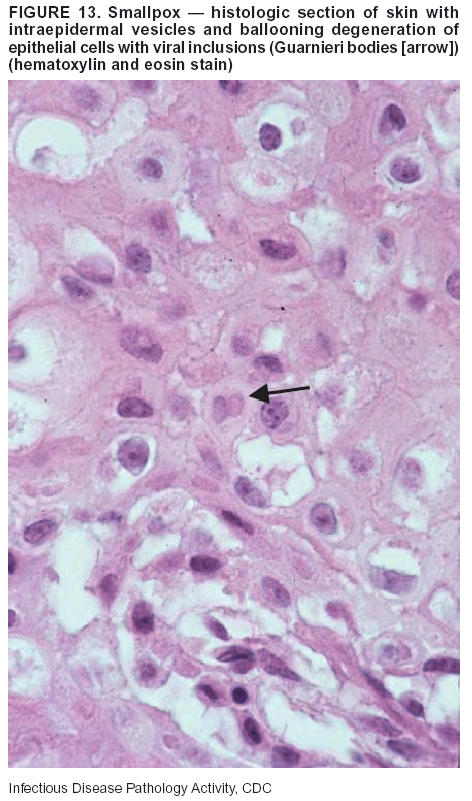

Pathologic Findings. Smallpox is an acute, highly contagious illness caused by a member of the Poxviridae family. Variola major refers to the form with a higher mortality rate, and variola minor or alastrim is a milder form. The lesions develop at approximately the same time and rate, starting in the palms and soles and spreading centrally; they first appear as macules and papules, and then progress to vesicles and umbilicated pustules (Figure 12), followed by scabs and crusts, and end as pitted scars. Occasionally, a hemorrhagic and uniformly fatal form occurs. This form has extensive bleeding into the skin and gastrointestinal tract and can be grossly taken for meningococcemia, acute leukemia, or a drug reaction (42). Microscopically, the skin exhibits multiloculated, intraepidermal vesicles; ballooning degeneration of epithelial cells; intracytoplasmic, paranuclear, and eosinophilic viral inclusions (i.e., Guarnieri bodies) (Figure 13); and occasionally intranuclear viral changes. Secondary infections (e.g., bronchitis, pneumonia, and encephalitis) can complicate the clinical appearance (43--48).